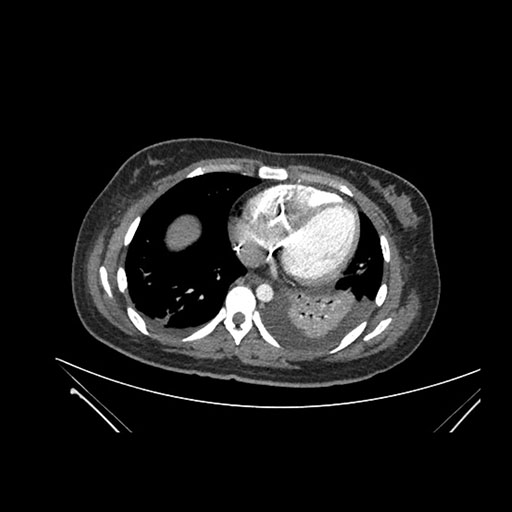

Axial Arterial

Axial Venous

Imaging analysis

Based on initial findings, which issue(s) would you be most concerned about?